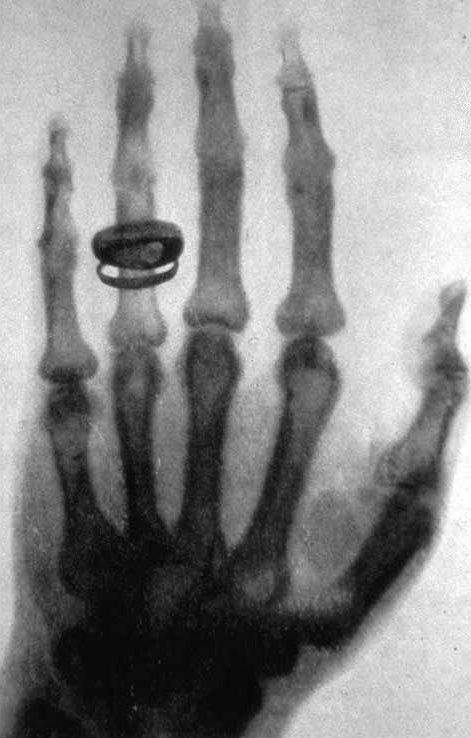

Uno dei momenti più celebri legati a questa scoperta è la prima radiografia della storia: la mano di sua moglie Bertha – con la fede nuziale ben visibile. Questa immagine mostrò per la prima volta ciò che era rimasto invisibile fino ad allora e dimostrò in modo impressionante il potenziale della nuova tecnologia.

Immagine: Wilhelm Conrad Röntgen, pubblico dominio via Wikipedia